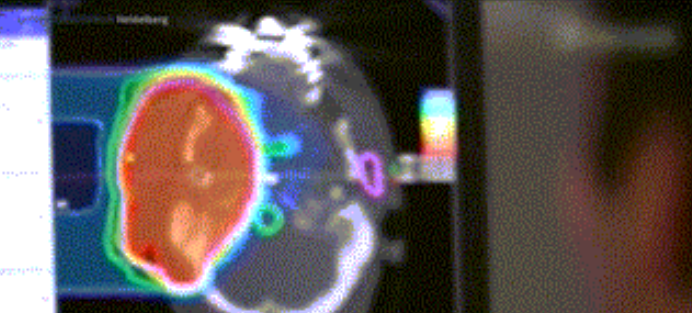

光柵掃描被集成到360°重離子治療一體機(jī)中,這種極其精確的照射方法以毫米為單位掃描腫瘤,可以保護(hù)健康組織且只治療腫瘤區(qū)域。

特別是腫瘤在高度輻射敏感位置或者諸如視神經(jīng)附近的復(fù)雜位置,可以通過選擇最佳射束入射角來減小這些器官的損傷。